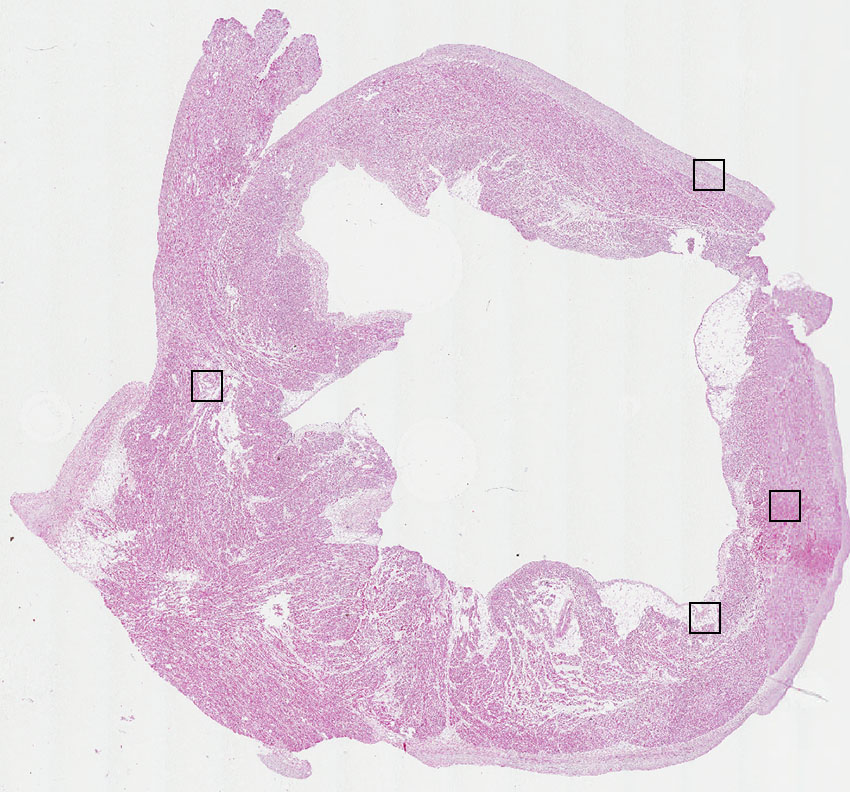

Myocytes:

20

Fibroblasts:

45

Endothelial cells:

30

Other cell types:

5